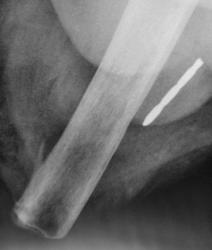

Иллюстрации 13, 14. В боковой проекции тень инородного тела чётко дифференцируется в «мягких тканях».